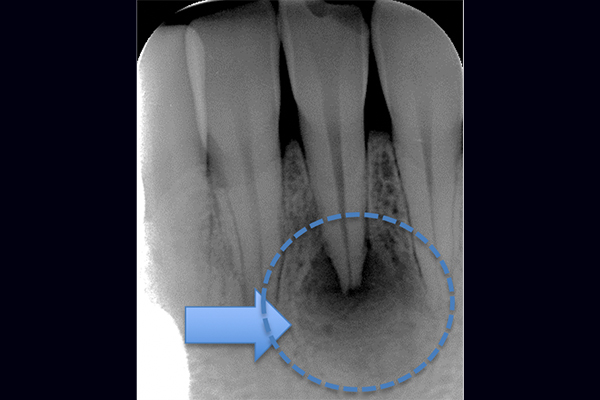

根の横に誤った穴をあけてしまい、気づかずに薬を入れてしまっている。また、器具が破折し、根の先に飛び出ている。

精密根管治療治療終了時歯の側面の穴と根尖はMTAにより緊密に封鎖した。

※本来の根管に薬が入ってることがわかります。